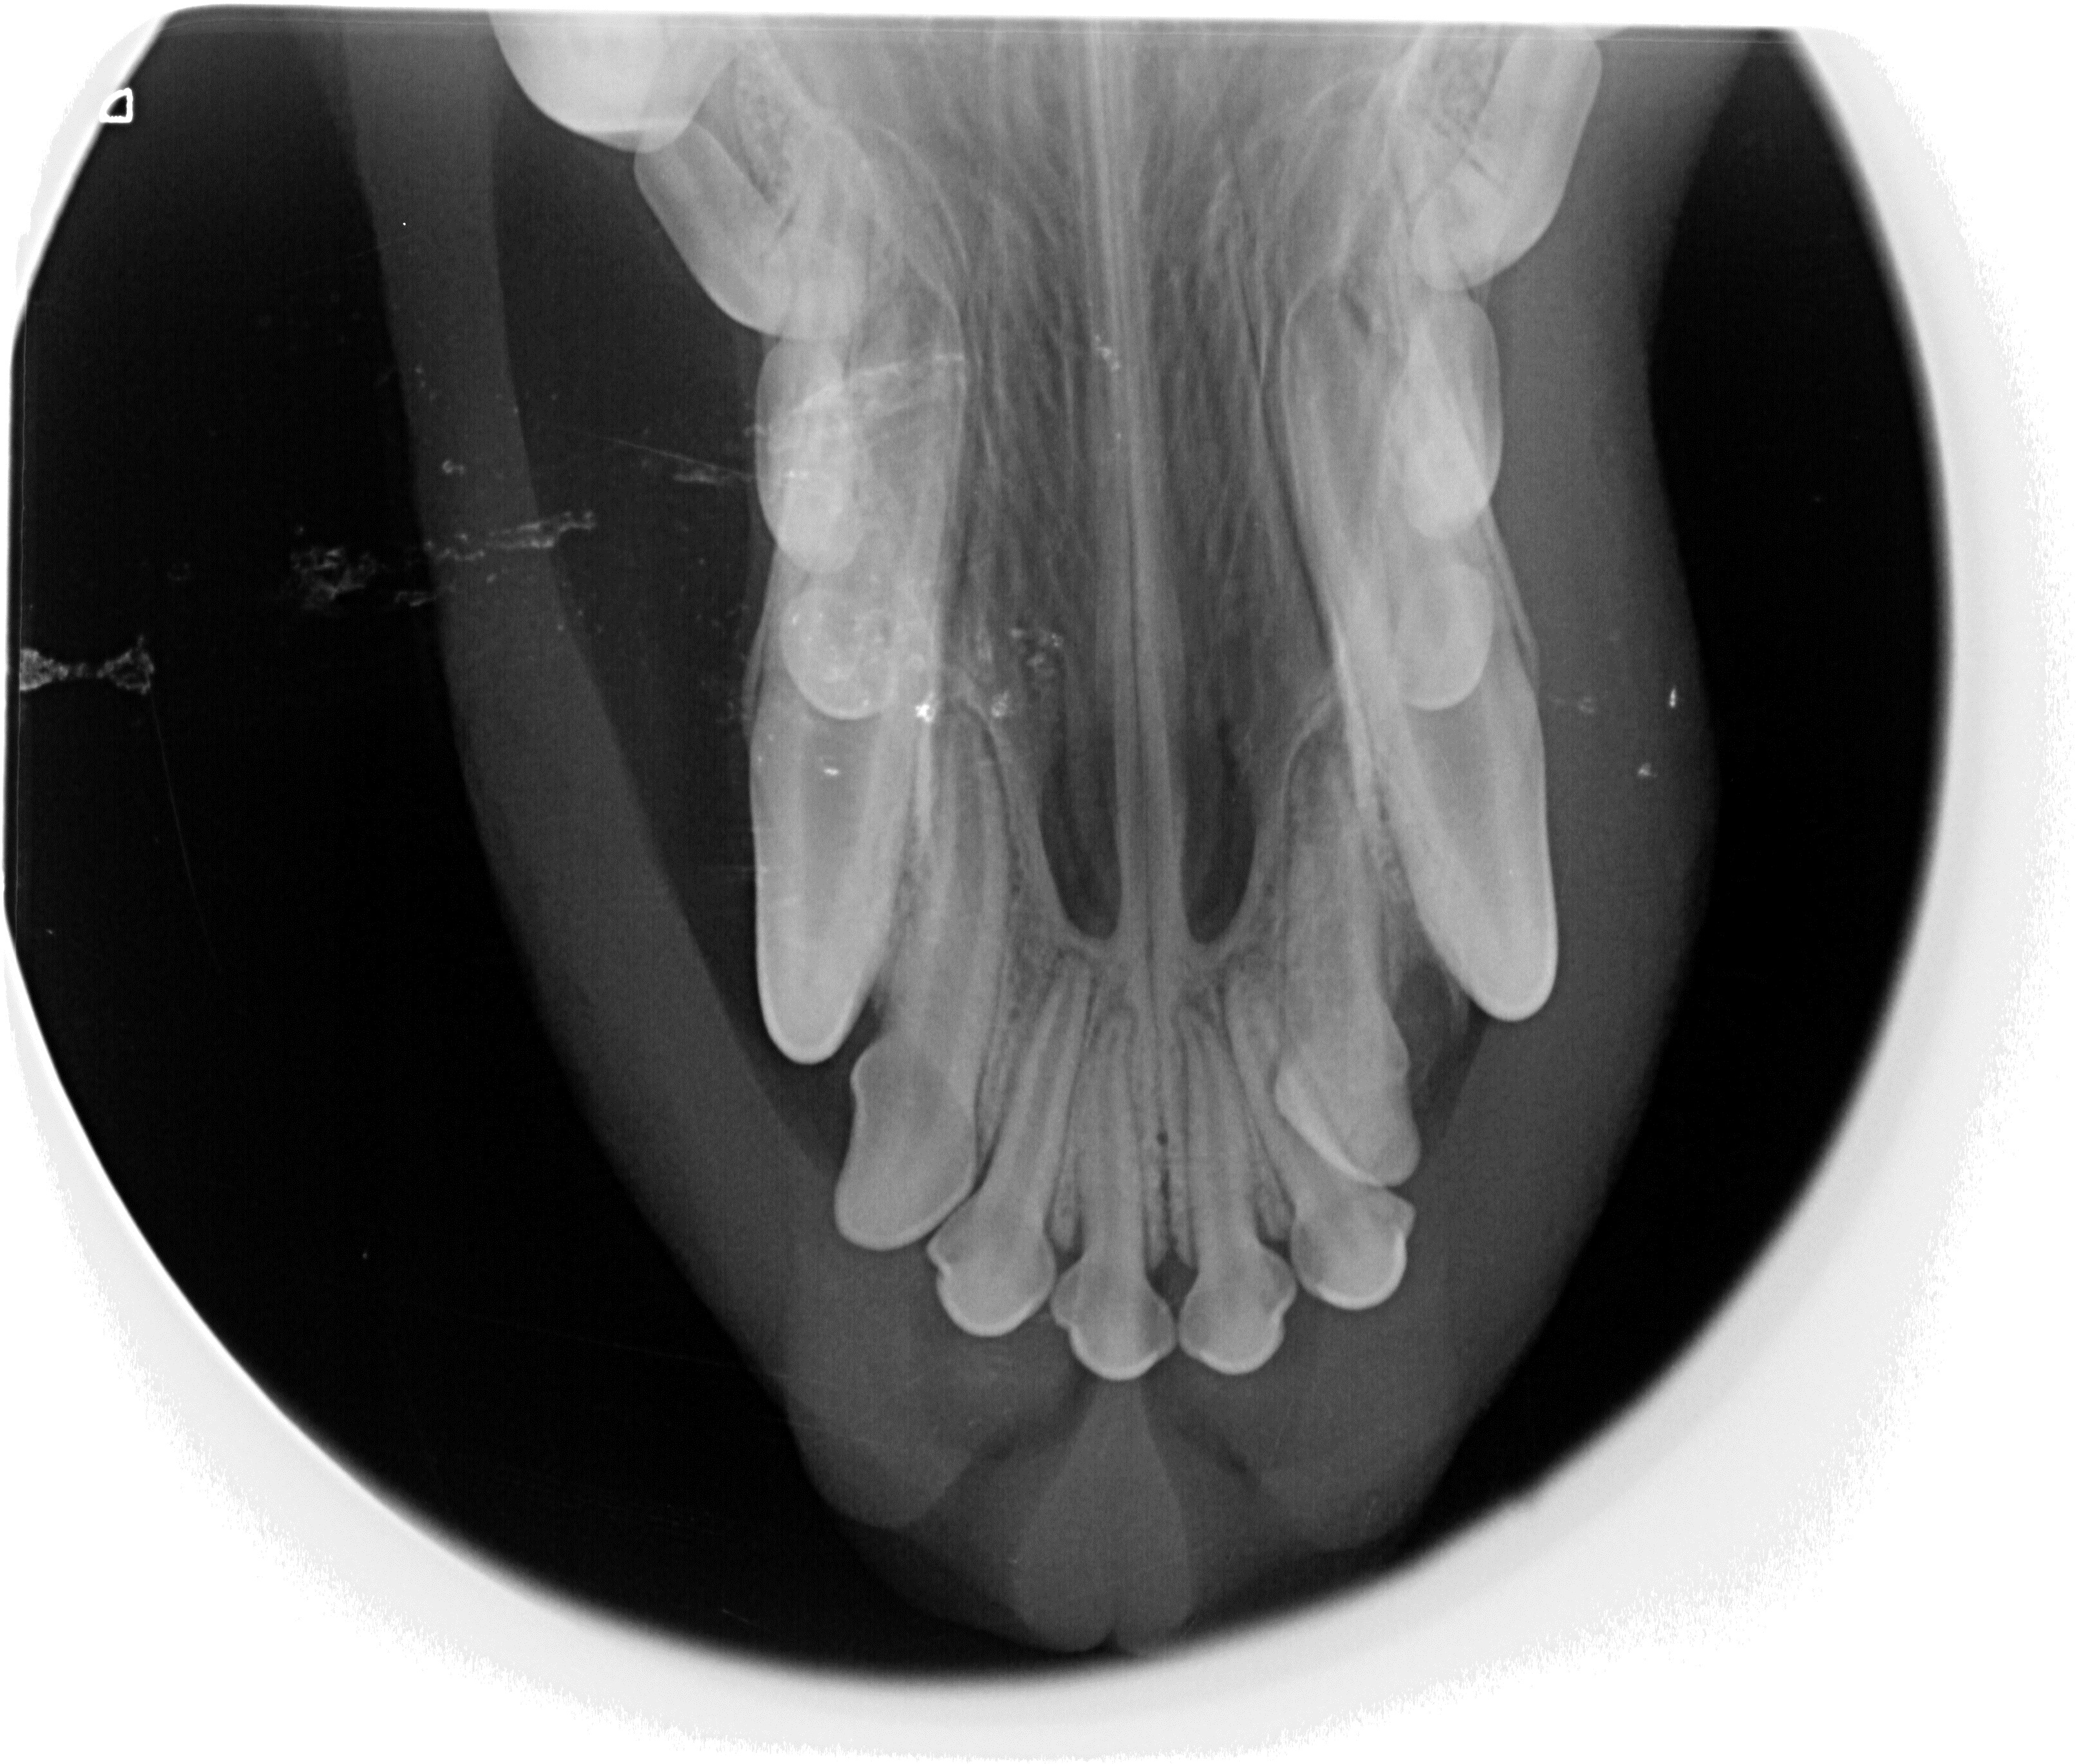

Hammasdigiröntgenkuvaus

Epäiltäessä hampaistossa tai leukaluissa vakavampia vaurioita, otetaan alueelta hammasröntgenkuvat diagnoosia ja jatkohoitosuunnitelmaa varten.